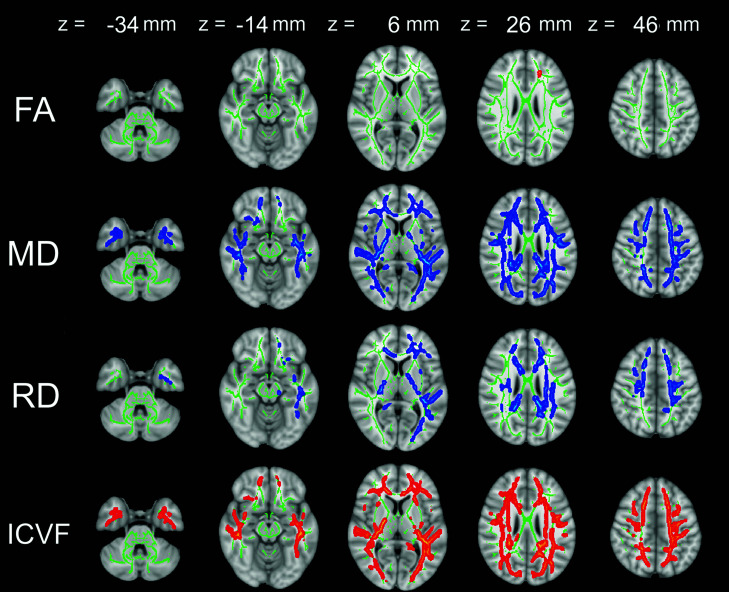

Results: TBSS analysis showed that patients with BMS had significantly higher FA and ICVF and lower MD and RD than the healthy control subjects (family-wise error [FWE] corrected P < 0.05). Changes in ICVF, MD, and RD were observed in widespread white matter areas. Fairly small areas with different FA were included. GBSS analysis showed that patients with BMS had significantly higher ISO and lower MD and RD than the healthy control subjects (FWE-corrected P < 0.05), mainly limited to the amygdala.

Abstract Image